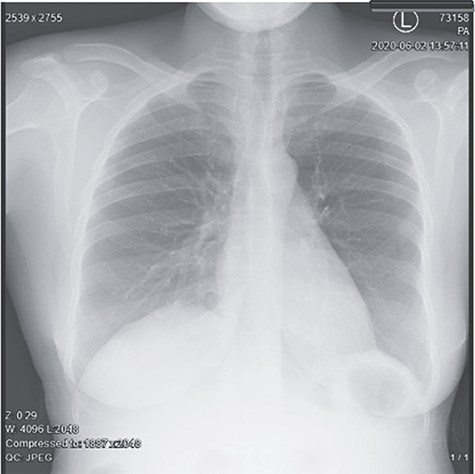

Abdominal pelvic ultrasound revealed ascitic fluid and enlarged uterus. Chest X-ray (Fig. 1) was normal. Computed tomography (Fig. 2) revealed cystic mass arising from left ovary measuring 15.6 × 7.1 × 6.1 cm with multiple soft masses in mesentery, omentum and umbilicus. Diagnosis of left ovarian tumor with peritoneal metastasis was suggested.